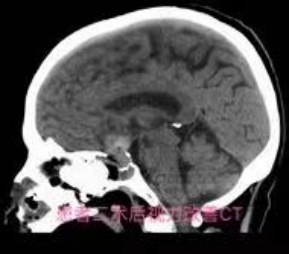

近段时间,自贡四院神经外科收治了几名垂体瘤患者,这几名患者的首要临床表现都是出现视物模糊,看东西重影,第一时间到眼科检查发现不是眼睛的问题,而是颅内垂体长了肿瘤。自贡四院神经外科的医生通过在神经内镜下经蝶鞍区将垂体瘤切除后,患者视力改善,恢复良好。